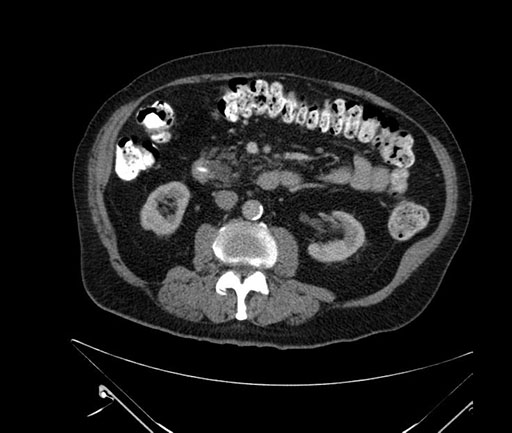

Coronal - stented